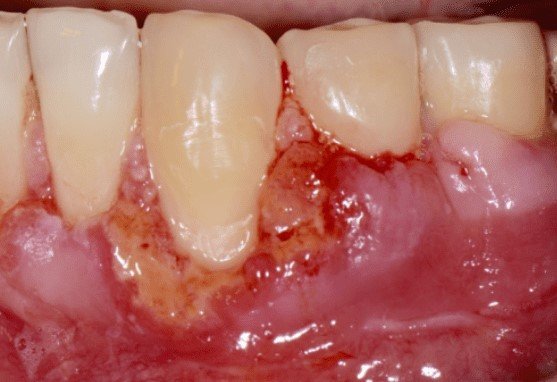

Signs of Gum Graft Failure

There are 6 clear signs of gum graft failure:

- Persistent white tissue sloughing

- Severe pain beyond 7 days

- Pus or infection at the surgical site

- Graft detachment or movement

- Increasing recession after surgery

- Prolonged redness and swelling

Immediate periodontal evaluation is required.

What does a failed gum graft look like?

A failed gum graft often appears as a large, non-pink patch of white or gray tissue that may eventually detach from the tooth.